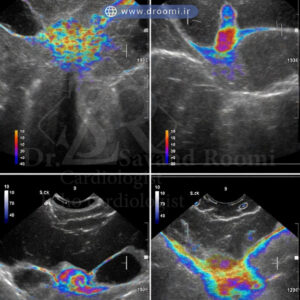

تصویر از انجام اکو داپلر رنگی که ارزیابی دقیق ساختار و عملکرد دریچههای قلب را نشان میدهد.

نحوه تشخیص بیماریهای دریچه با اکو داپلر رنگی

اکوکاردیوگرافی داپلر رنگی یکی از پیشرفتهترین ابزارهای تشخیصی در پزشکی قلب است که امکان ارزیابی دقیق ساختار و عملکرد دریچههای قلب را فراهم میکند. این روش با ترکیب تصاویر دوبعدی قلب و نمایش رنگی جریان خون، پزشکان را قادر میسازد تا مشکلات دریچهای را با جزئیات بالا شناسایی کنند. در کلینیک دکتر سوندرومی، تشخیص و درمان بیماریهای دریچه قلب در شیراز با استفاده از این فناوری مدرن انجام میشود و به بیماران کمک میکند تا بدون نیاز به روشهای تهاجمی، ارزیابی کاملی دریافت کنند. تصاویر اکو داپلر رنگی دریچههای قلب نقش کلیدی در این فرآیند دارند و اطلاعات دینامیکی از جریان خون ارائه میدهند.

نمایش جریان خون معکوس و سرعت غیرطبیعی با رنگ

یکی از ویژگیهای برجسته اکو داپلر رنگی، نمایش جریان خون به صورت رنگی است: معمولاً رنگ قرمز برای جریان به سمت پروب (سنسور) و آبی برای جریان دورشونده استفاده میشود. در موارد تشخیص نارسایی دریچه قلب با اکو رنگی، جریان خون معکوس (رگورژیتاسیون) به صورت جت رنگی مشخص ظاهر میشود که شدت و جهت آن را نشان میدهد. همچنین، در تنگی دریچه، سرعت غیرطبیعی جریان خون با رنگهای روشنتر (مانند زرد یا سفید) نمایان میگردد که نشانه turbulence (تلاطم) است.

این قابلیت بصری به بهترین متخصص اکوکاردیوگرافی دریچه قلب شیراز اجازه میدهد تا مشکلات را در لحظه تشخیص دهد و از تفسیرهای اشتباه جلوگیری کند.

اندازهگیری شدت نارسایی و تنگی (خفیف، متوسط، شدید)

اکو داپلر رنگی برای تنگی آئورت و نارسایی، ابزار دقیقی برای طبقهبندی شدت مشکل است. شدت نارسایی اغلب بر اساس اندازه جت رنگی، حجم regurgitant و پارامترهایی مانند vena contracta اندازهگیری میشود: خفیف (جت کوچک)، متوسط (جت متوسط با تأثیر بر عملکرد قلب) و شدید (جت بزرگ با علائم نارسایی قلبی). در تنگی دریچه، سرعت حداکثری جریان و گرادیان فشار محاسبه میشود تا درجه استنوز تعیین گردد.

این اندازهگیریها بر اساس راهنماهای انجمن قلب آمریکا (AHA) و جامعه اکوکاردیوگرافی اروپا انجام میشود و دقت بالایی در پیشبینی نیاز به مداخله درمانی دارد. اکو رنگی قلب برای دریچه میترال به ویژه در ارزیابی نارسایی میترال مفید است و شدت آن را به طور کمی تخمین میزند.

نمونه تصاویر واقعی داپلر رنگی از مشکلات دریچه

برای درک بهتر، در ادامه نمونههایی از تصاویر اکو داپلر رنگی دریچههای قلب واقعی آورده شده است که مشکلات رایج را نشان میدهند:

تصویر نمونه از جت رگورژیتاسیون میترال (نارسایی دریچه میترال) با جریان خون معکوس رنگی

نمایش اجزای رنگی در اندازهگیری نارسایی میترال

پرولاپس دریچه میترال با جریان مرتبط در اکو داپلر رنگی

مقایسه تنگی دریچه آئورت با حالت طبیعی در اکو رنگی

نارسایی دریچه تریکوسپید با جت رنگی

کلاژی از تصاویر اکو داپلر رنگی که انواع شایع بیماریهای دریچهای قلب را نمایش میدهد.

این تصاویر به پزشکان کمک میکنند تا تشخیص دقیقتری داشته باشند و در کلینیکهای پیشرفته مانند دکتر سوندرومی قابل مشاهده هستند.